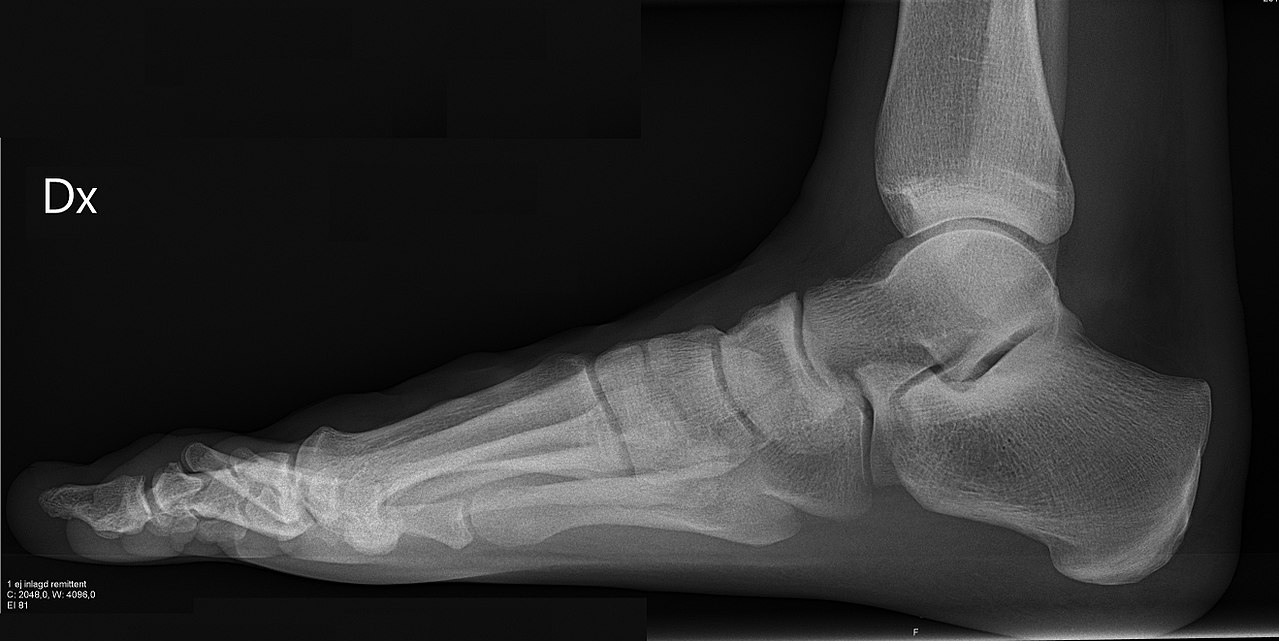

Ankle and foot phantom with talus, calcaneus, tarsal bones, Achilles tendon, and lateral ligaments